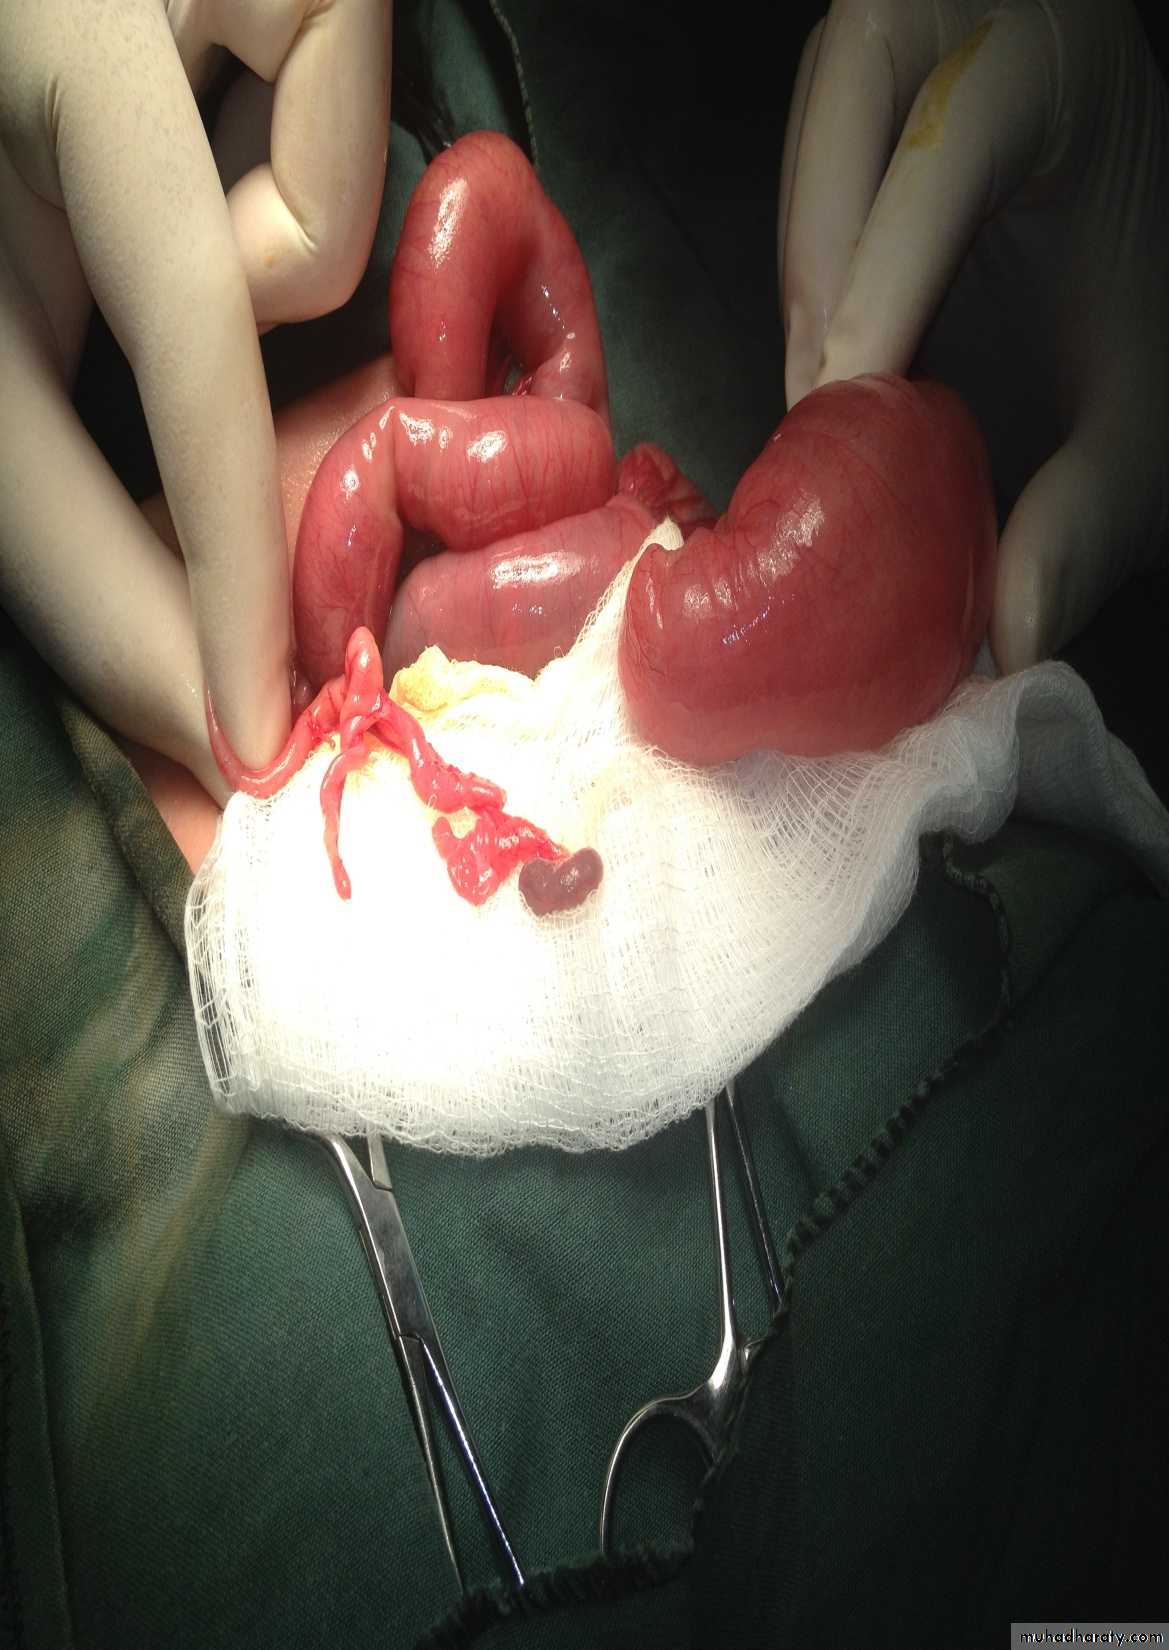

Abdominal Wall Defects